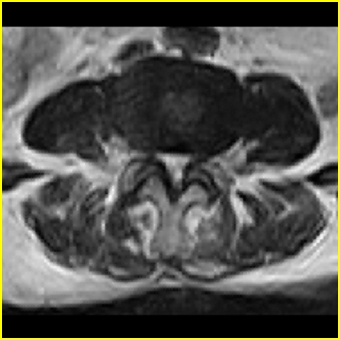

右侧黄韧带肥厚或钙化,压迫马尾神经所致。必要时行ct扫描。

我认为这一层面椎间盘应该合并左外侧型突出。

黄韧带肥厚.